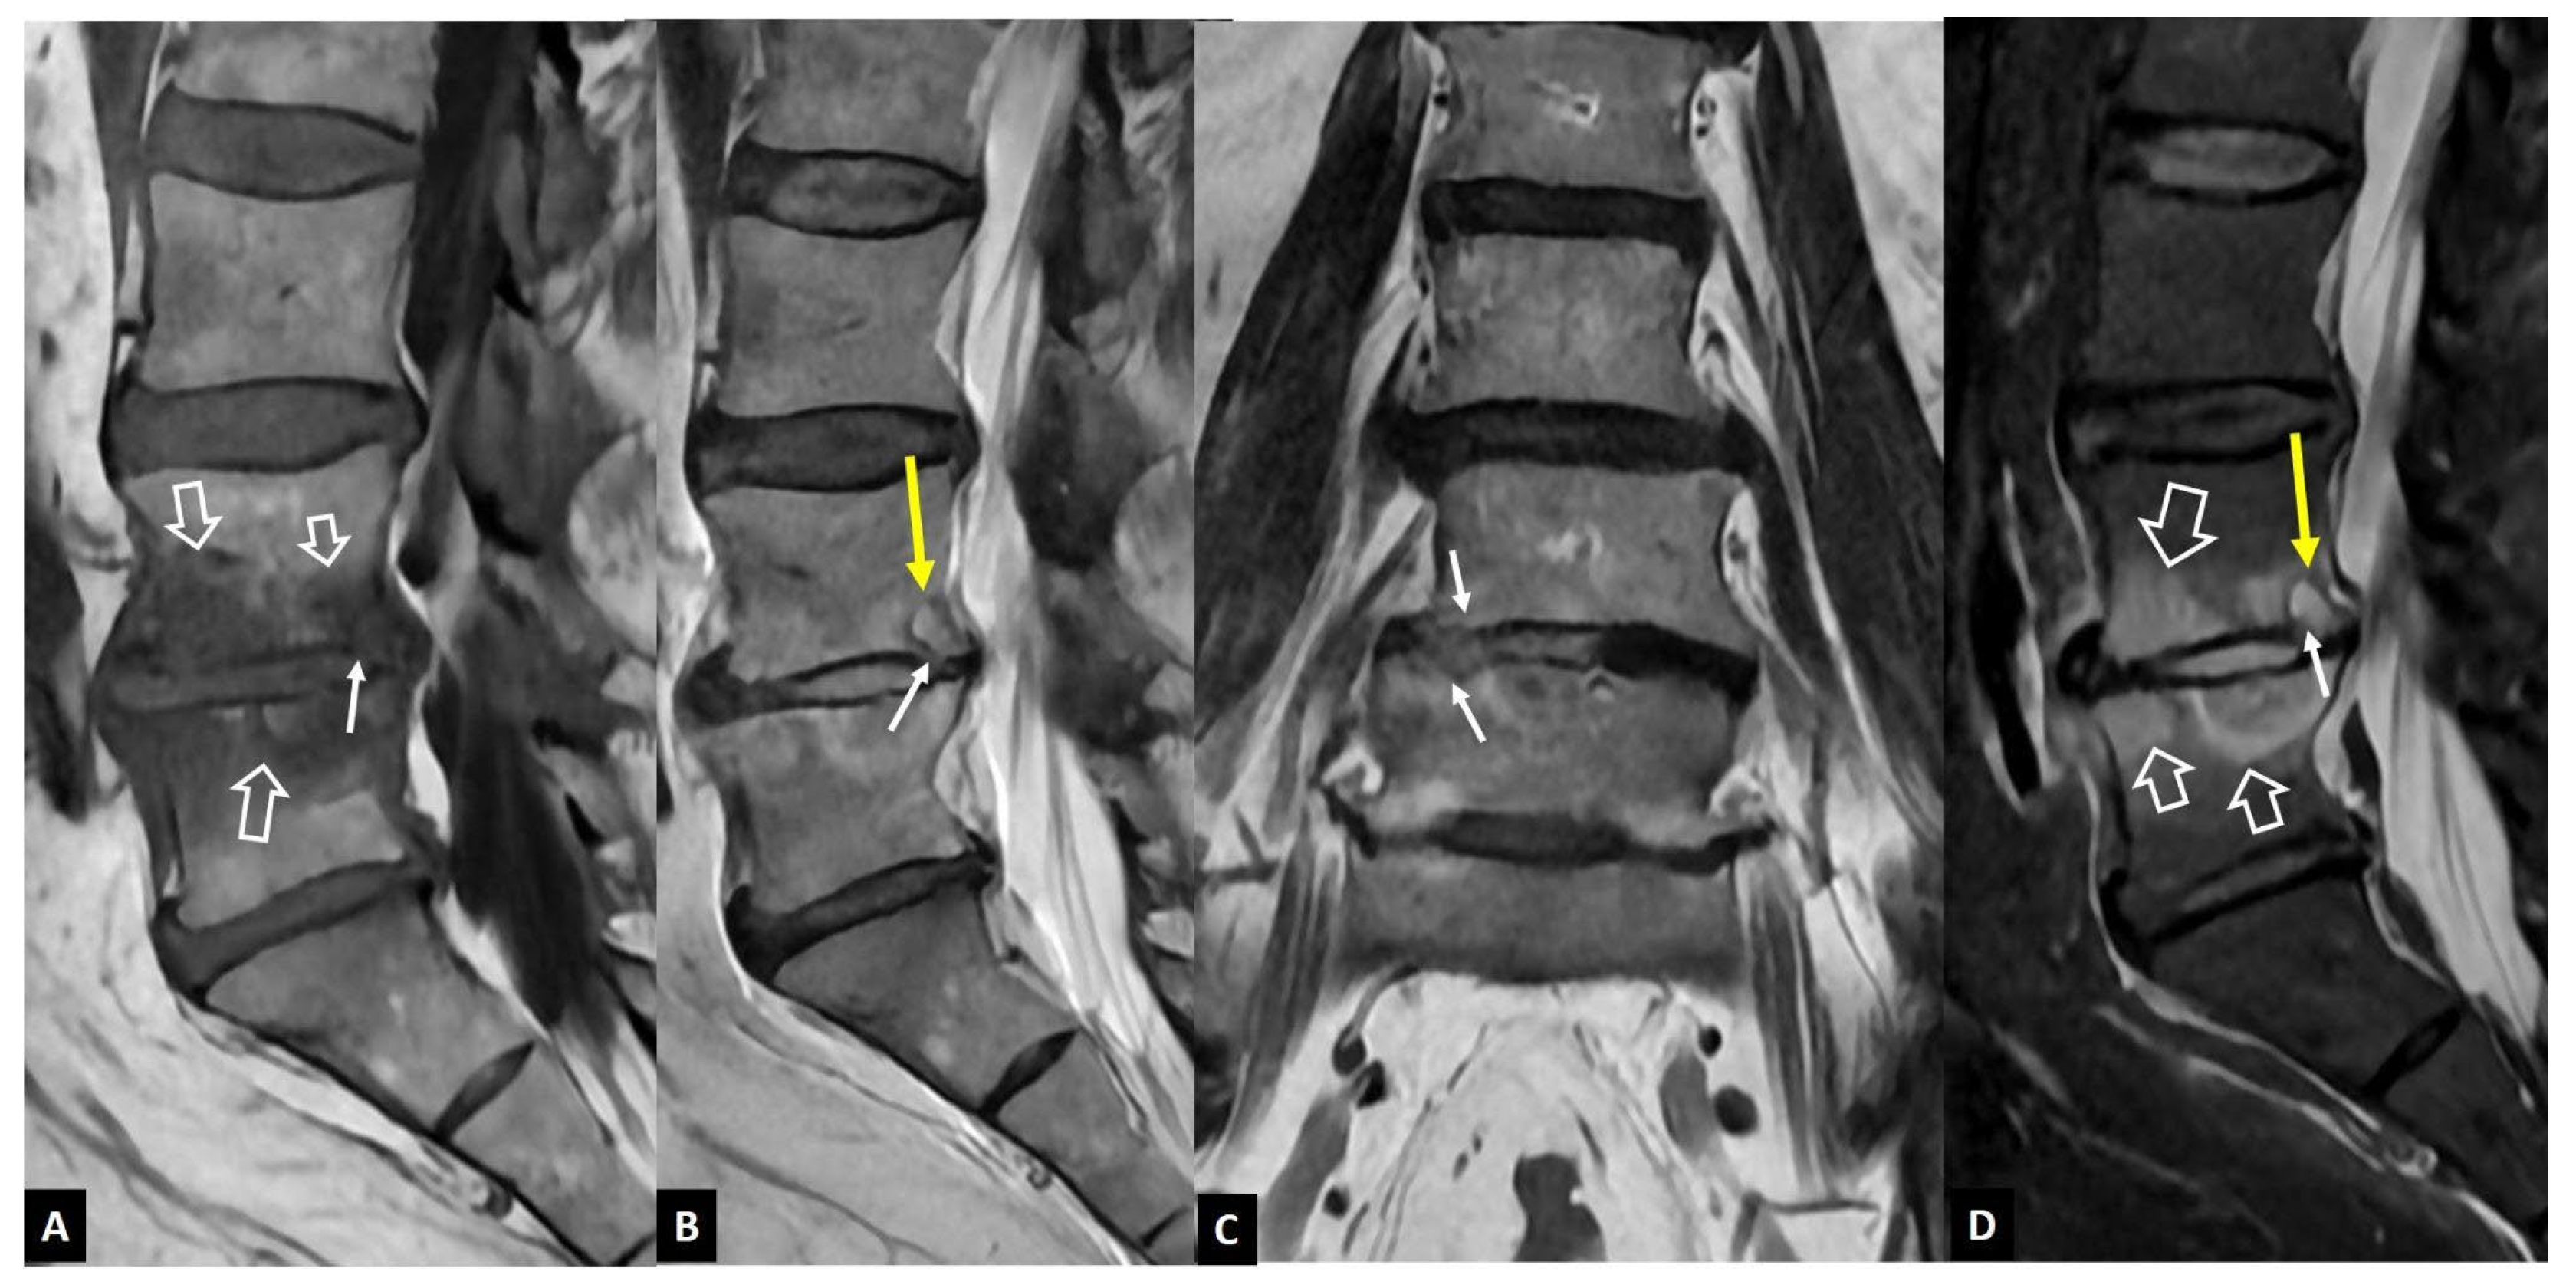

1. a.i. Modic I Changes

1. a.ii. Aseptic Spondylodiscitis

1. a.iii. SAPHO Syndrome

1. a.iv. Destructive Spondyloarthropathy